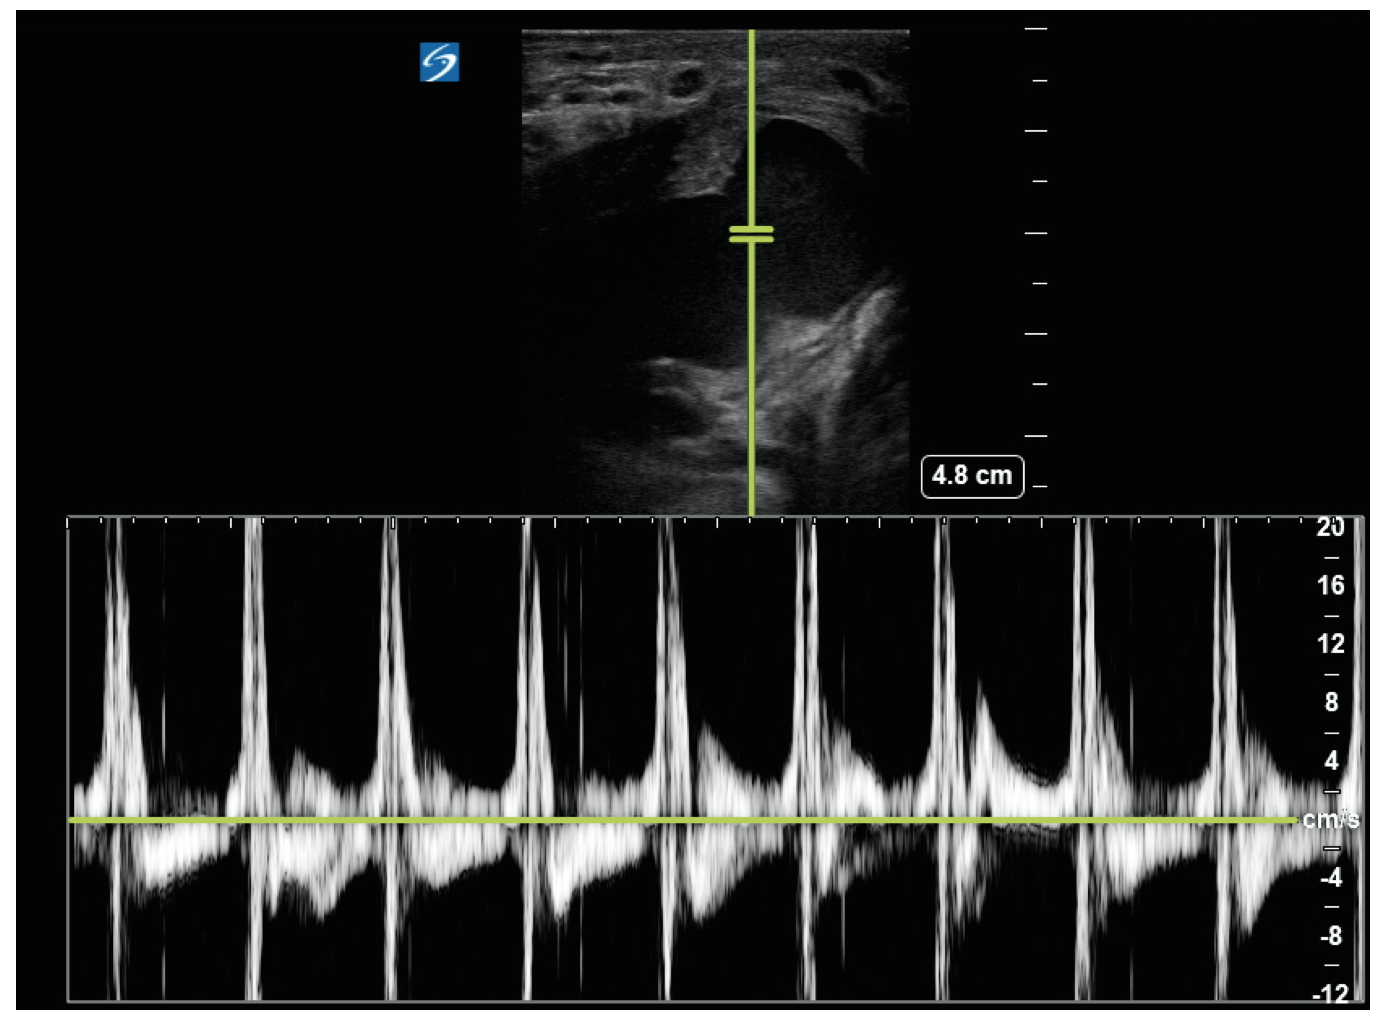

Figure 3. Pulsed wave Doppler overlying the neck of the mass on bedside ultrasound showing pulsatile flow.

The diagnosis of a pseudoaneurysm may be confirmed with color Doppler ultrasonography, computed tomography, or angiography.5 There are 3 classic signs of a pseudoaneurysm in sonography: a communication between the artery and the pseudoaneurysm (Fig.1); a yin-yang sign, which indicates bidirectional flow because of the swirling of blood within the pseudoaneurysm cavity (Fig. 2); and a “to-and-fro” on pulsed wave doppler within the neck, indicating reversal of flow in the neck during diastole (Fig. 3). Bedside ultrasonography has a sensitivity and specificity of 94% and 94%-97%, respectively in the evaluation of possible vascular injury causing pseudoaneurysm,6 and should be performed prior to consideration of incision and drainage of what might otherwise appear to be an abscess.